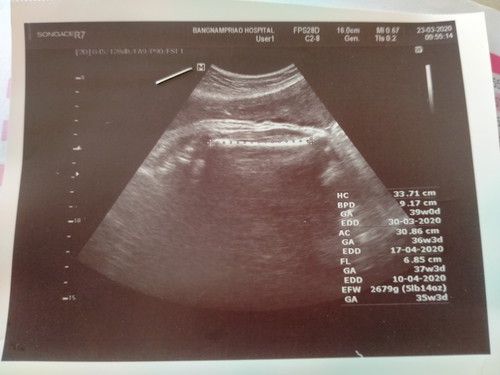

รบกวนคุณแม่ๆช่วยดูทีค่ะว่า..ในใบซาวด์ของเราคุณหมอกำหนดคลอดให้วันไหนคะ..พอดีมีนมี3ช่วงก็เลยไม่แน่ใจค่ะ

ในสมุดลมพูบอกวันไหนค่ะ ในใบซาว ที่เหนหลายอันคือคาดคะเนจากส่วนต่างๆของน้องค่ะ มันเลยไม่เท่ากัน เพราะตอนนี้น้องก้สองโลหก